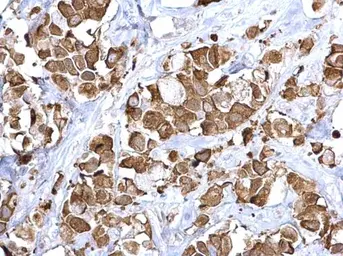

Anti-Fatty Acid Synthase antibody [N1], N-term used in IHC (Paraffin sections) (IHC-P). GTX109833

GTX109833 IHC-P Image

Fatty Acid Synthase antibody [N1], N-term detects Fatty Acid Synthase protein at cytoplasm on human breast carcinoma by immunohistochemical analysis.

Sample: Paraffin-embedded human breast carcinoma.

Fatty Acid Synthase antibody [N1], N-term (GTX109833) diluted at 1:500.

Antigen Retrieval: Trilogy™ (EDTA based, pH 8.0) buffer, 15min